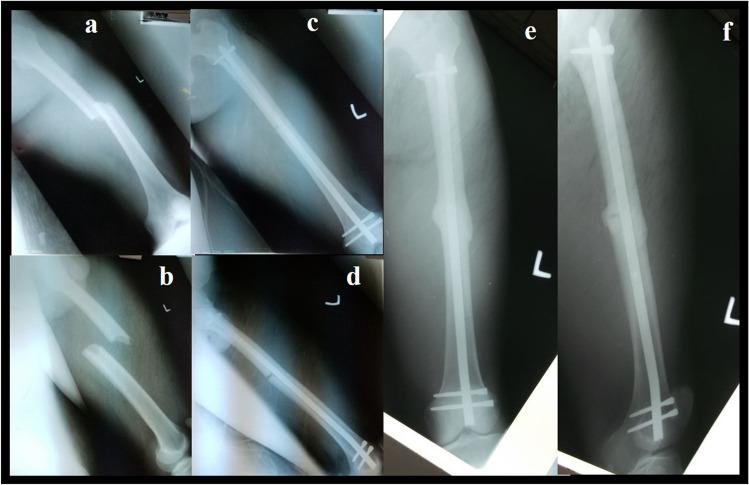

Femoral fractures are common in low and middle-income countries (LMIC), predominantly caused by high-energy trauma. The surgical implant generation network (SIGN®) program offers two different intramedullary nails in LMIC which are designed to be used without image intensifier free of charge for the patients: the SIGN standard nail (SSN®) and the SIGN Fin nail (SFN®). This study aimed to compare the results of the SSN® and the SFN® for the treatment of middle and distal shaft femoral fractures through a retrograde approach.

This was a retrospective, descriptive, and non-experimental study including all consecutive patients who underwent surgical management of middle or distal shaft femoral fracture between January 2017 and May 2022 in an NGO hospital located in Freetown, Sierra Leone. The duration of surgery, type of reduction, complications like screw loosening, implant migration, anterior knee pain and non-union rate at six months of follow up were evaluated.

A total of 122 patients were included in the study. Group A: 60 patients were managed with SSN® and Group B: 62 patients with SFN®. The mean operative time was 104 min with SSN® and 78 with SFN® (p < 0.001). Open reduction of the fracture was necessary in ten (16.7%) patients with SSN® and 12 (19.4%) patients treated with SFN® (p = 0.69). Non-union was observed in one (1.7%) patient with SSN® and two (3.2%) patients with SFN® (p = 0.57).

Both options seem equally effective in treating midshaft and distal femoral shaft fractures. The SFN® reduces the surgical time, due to this fact, in polytraumatized patients, patients with bilateral femur fracture or patients with ipsilateral tibia fracture, it can be considered as the best option to be used. There was no statistical difference in the complications presented by the two groups.